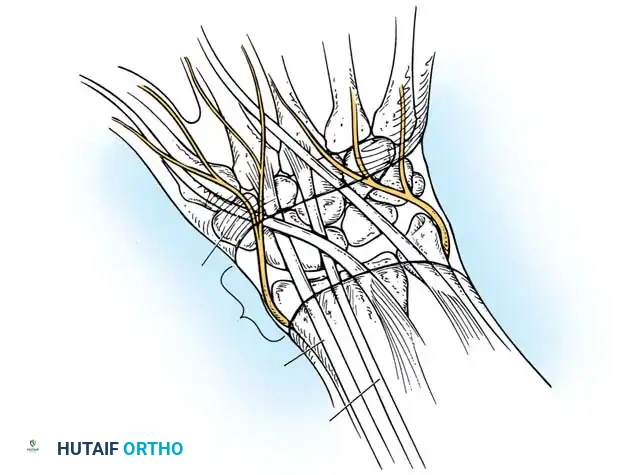

Surgical Warning: The radial artery frequently arborizes around or directly through the lobules of a volar ganglion. Meticulous dissection under loupe magnification is mandatory.

- Incision: Under tourniquet control, make a longitudinal or lazy-S incision centered over the ganglion, typically situated just radial to the FCR tendon. Carefully avoid injury to the palmar cutaneous branch of the median nerve, which lies ulnar to the FCR.

- Arterial Dissection: Dissect the radial artery carefully under loupe magnification. Retract the artery radially using vessel loops.

- Cyst Mobilization: Dissect the ganglion cyst using blunt and sharp dissection in a proximal-to-distal direction. Carry the dissection down along the stalk to its origin, which is usually at the radiocarpal or scaphotrapezial joint.